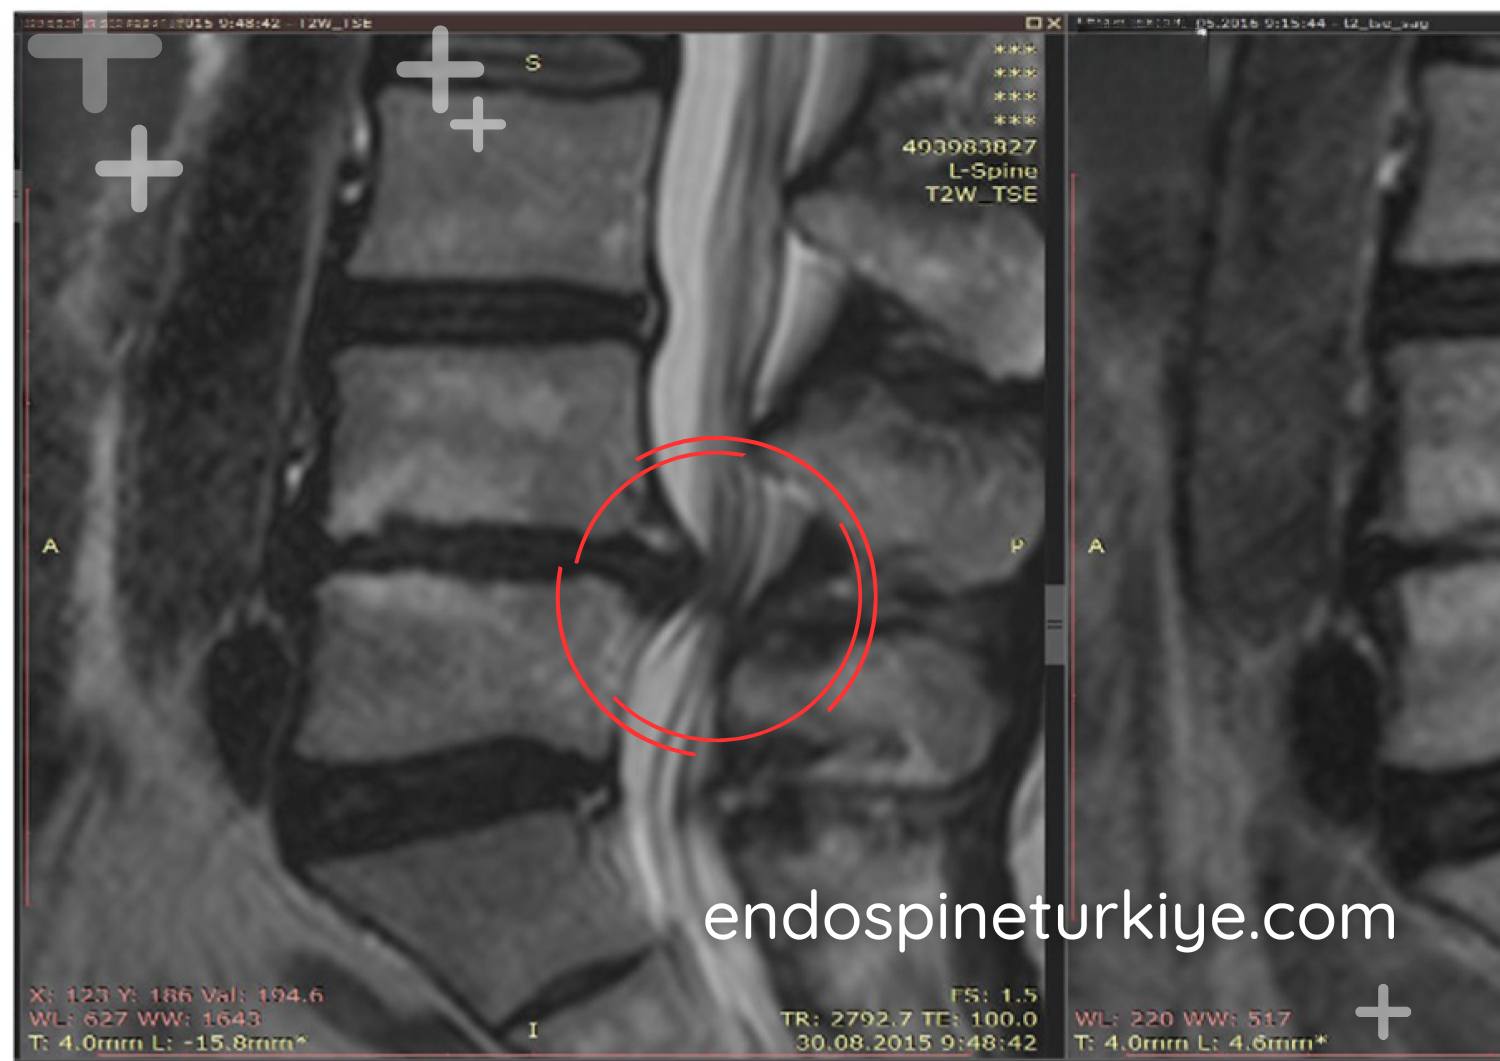

Bel fıtığı tedavi öncesi MR görüntüsü - L4-L5 disk hernisi

Tedavi Öncesi

Disk basıncı yüksek

Lazerle bel fıtığı tedavisi sonrası MR görüntüsü - PLDD sonucu

Tedavi Sonrası

Basınç normale döndü